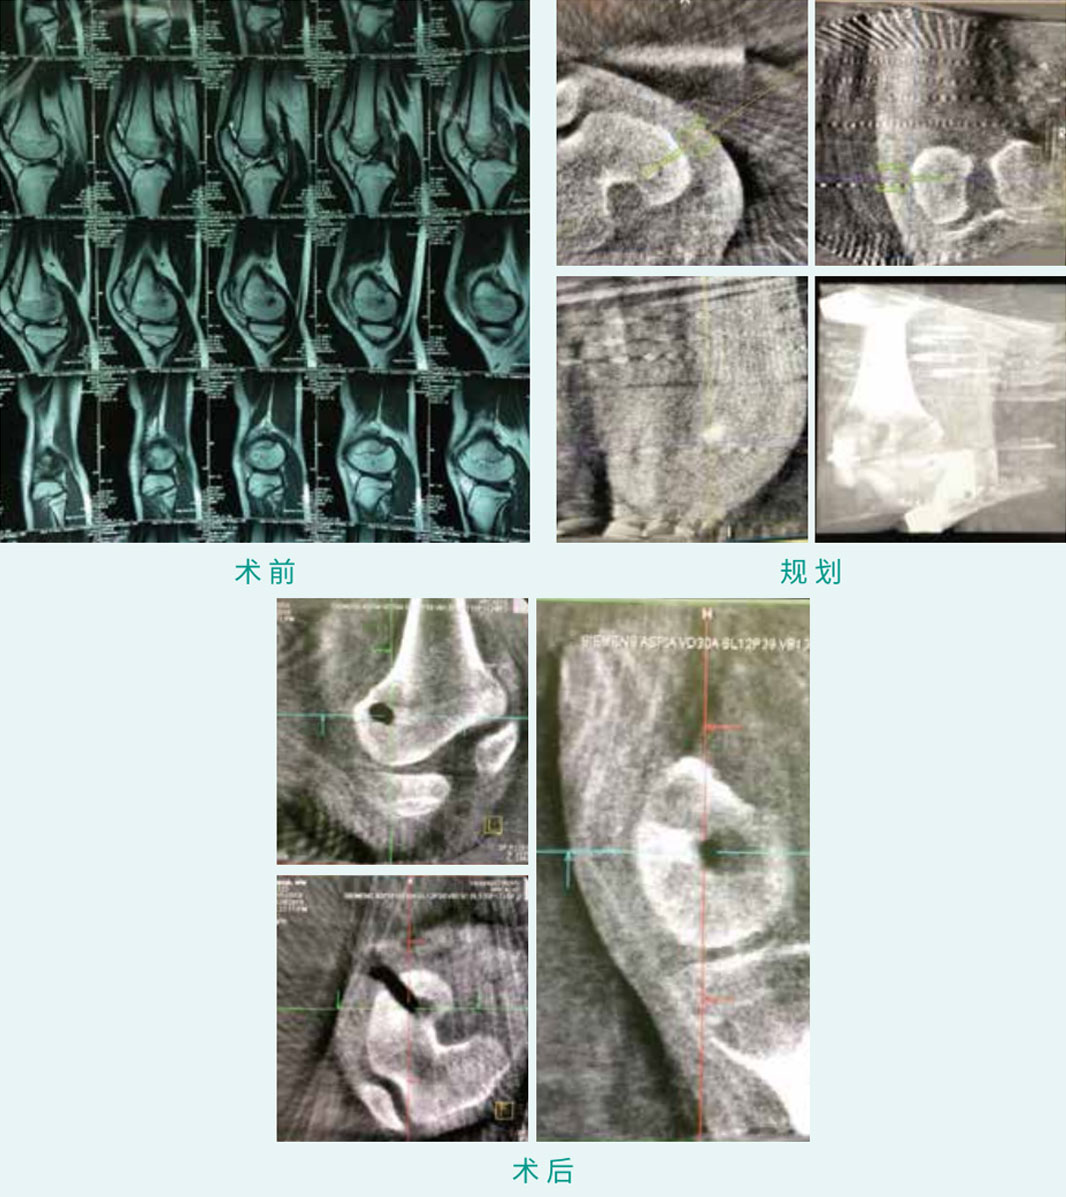

基本情形:患子女,,,,,,13岁,,,,,,股骨髁骨肿瘤

机械人累积用时:20分钟

病例泉源:佛山市中医院 劳永锵